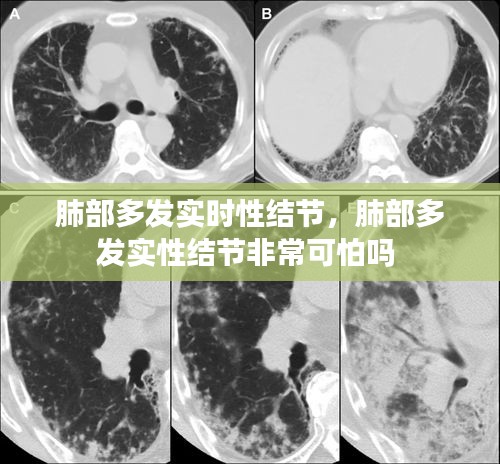

肺部多发实时性结节是指在肺部检查中发现的一种影像学表现,通常指的是在X光、CT扫描或其他影像学检查中,肺部出现多个直径小于3厘米的结节。这些结节可能是良性的,也可能是恶性的,因此对于医生和患者来说,及时诊断和治疗至关重要。

• 影像学检查:X光、CT扫描、MRI等影像学检查是诊断肺部结节的主要手段。